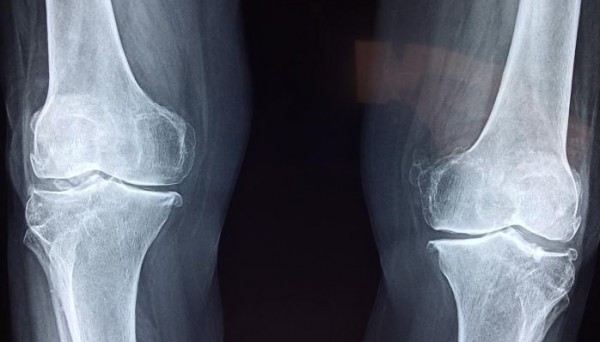

إن مرض التهاب المفاصل شائع ومؤلِم وينتج عن تلف مفاصل المريض، وعلى الرغم من أن حشوات الغضاريف عادة ما تخفف الألم في تلك النقاط، إلا أن الإصابات أو التقدم في السن يمكن أن يتسبب في تآكلها.

مع تدهور حالة الغضروف، تبدأ العظام في الاصطدام ببعضها البعض، وبالتالي يعاني المريض من ألم رهيب عند ممارسة الأنشطة اليومية مثل المشي، لذا فإن نمو الغضروف الجديد هو المفتاح لجعل الحالة أقل إيلامًا.